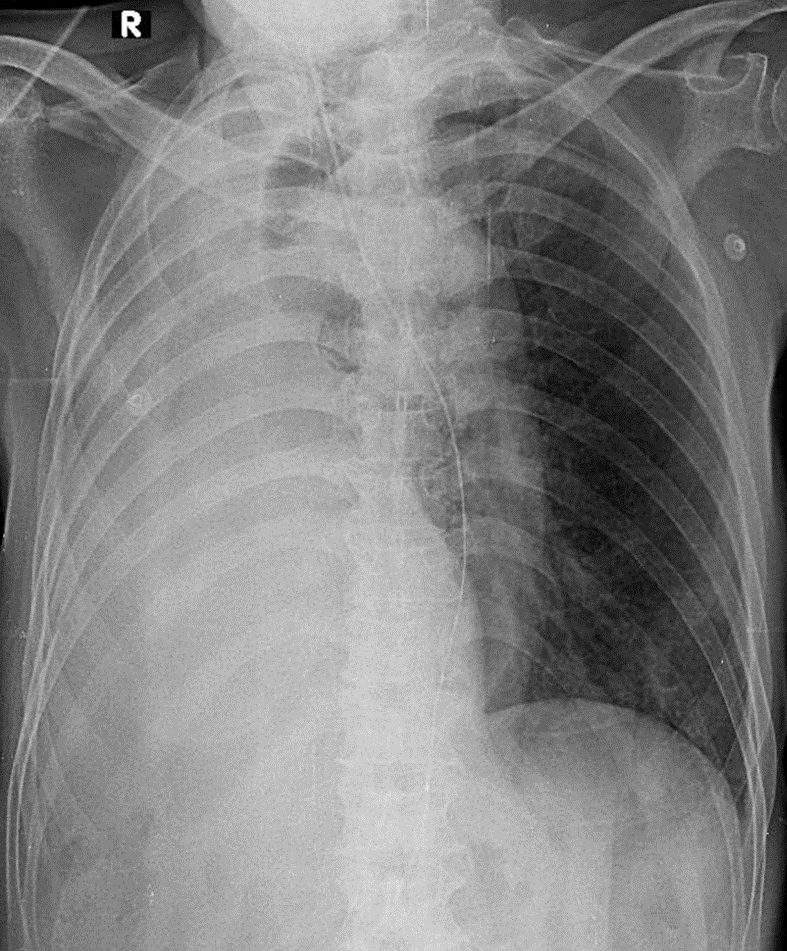

1-Khí quản kéo lệch sang (P) 2-Xẹp phổi (P) kéo bóng tim trung thất lệch(P)